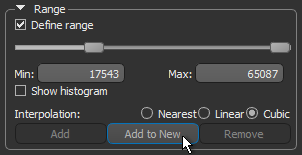

- Select the Define range option in the Range box on the ROI Tools panel.

- Drag the left or right Range sliders to change the minimum or maximum values of the intensity range or enter the required values in the Min and Max edit boxes.

- Click the Add to New button to create a region of interest in which all voxels within the selected range are labeled.

- Uncheck the Define range option in the Range box.